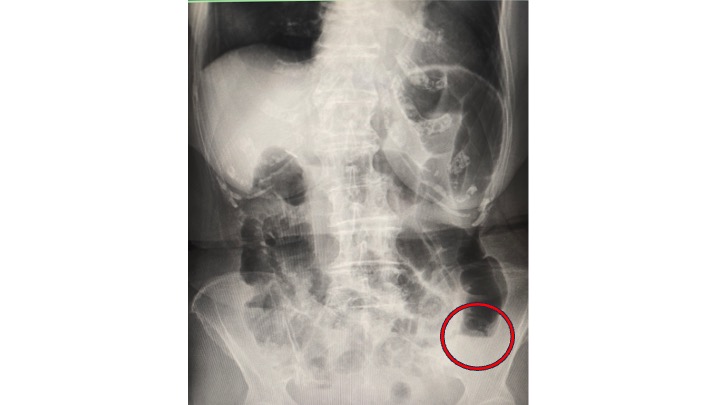

腹部レントゲンを取ると、大腸全体に貯留するガスと、一部小腸ガスを認め、”イレウス(腸閉塞)”と診断しました。

S状結腸ないし下行結腸に赤丸で示す、閉塞機転を認めます。

その原因は・・・

に大別されます。①は所見として合わず。

③糞石 > ②大腸癌 の可能性を考慮しました。